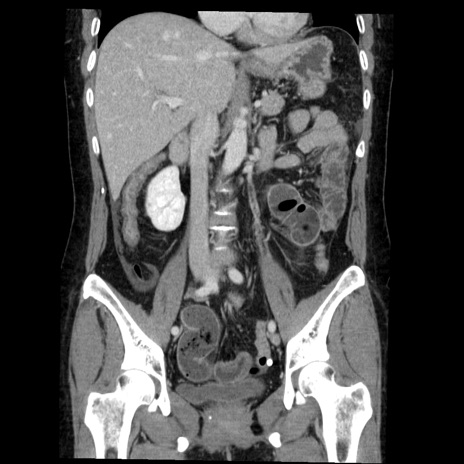

症例6(冠状断像)

【症例】50歳代女性

【主訴】下腹部痛

【既往歴】卵巣癌術後(8年前に当院で卵巣摘出)